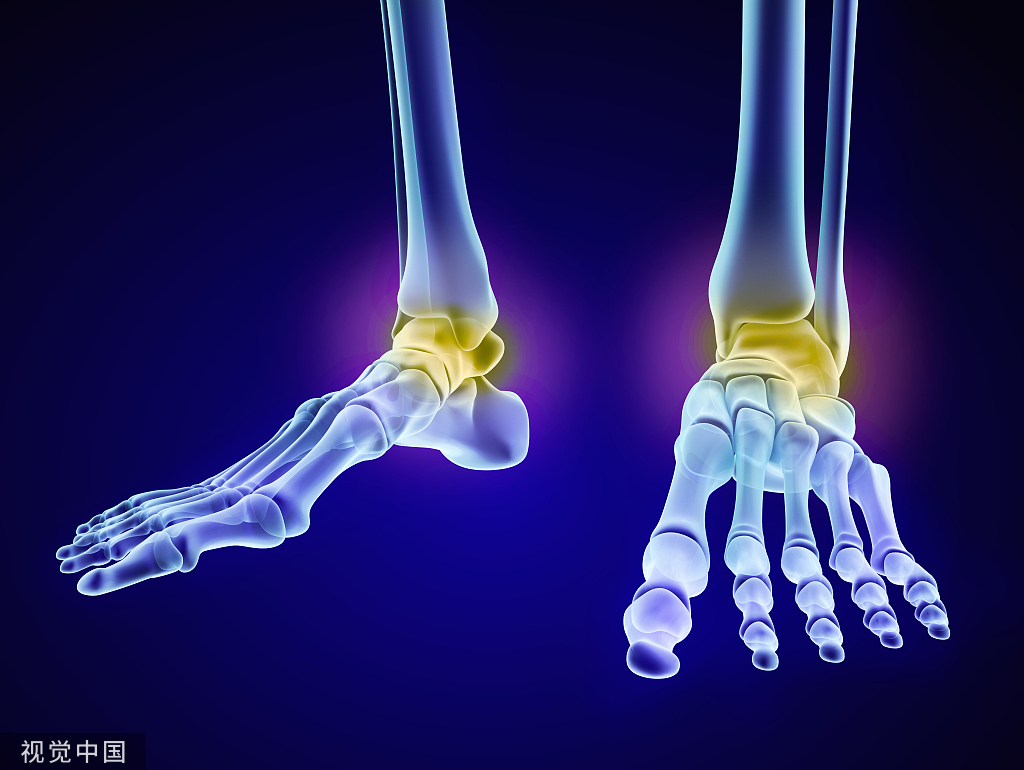

骨质疏松症是全身骨骼成分减少的一种现象,就是破骨细胞把骨头吃掉了,主要表现为骨组织内单位体积中骨量减少,由于骨质疏松症病程缓慢而常被忽略,直到发生骨折,被称为寂静的杀手

总之老年人驼背,易骨折,身高变矮,腰背部疼痛,四肢关节痛,足跟部疼痛以及肢体出现刺痛、麻木感,小心这些骨质疏松初期的表现。